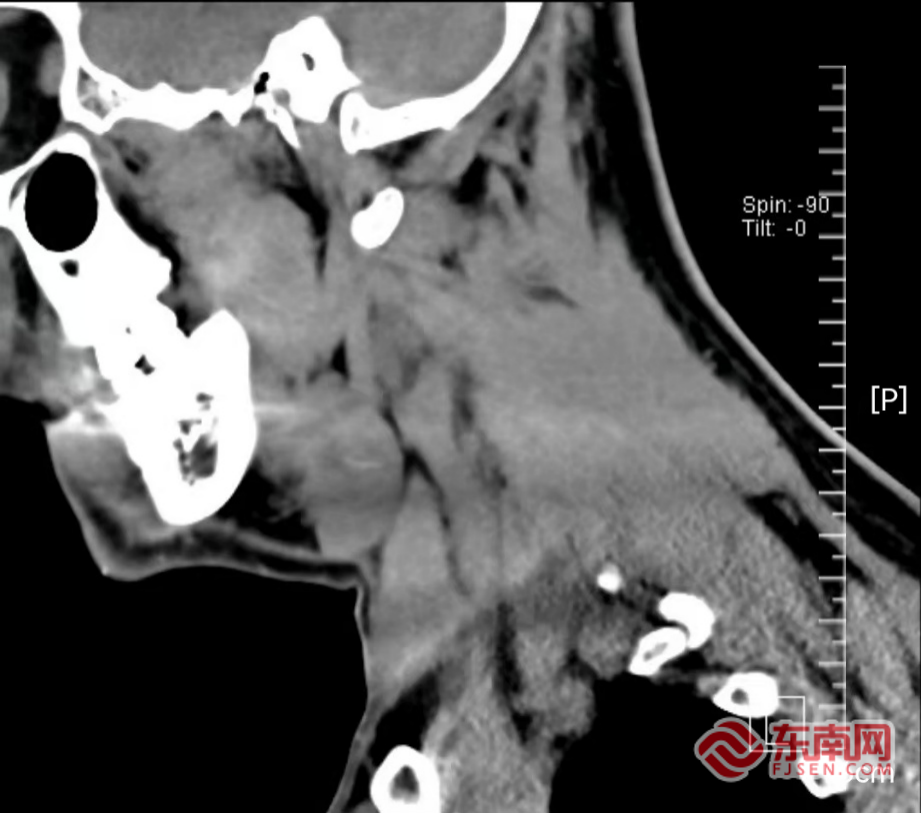

术后影像图。宁德市医院供图

手术过程比预想的更具挑战。医生小心翼翼切除受侵的下颌下腺组织后,将腺体组织一点点切开仔细探查、细致分离,最终在腺体组织中找到小小的鱼刺。当鱼刺被成功取出时,孙先生悬了一个月的心终于落了地,困扰他许久的咽痛和异物感也终于得到解决。